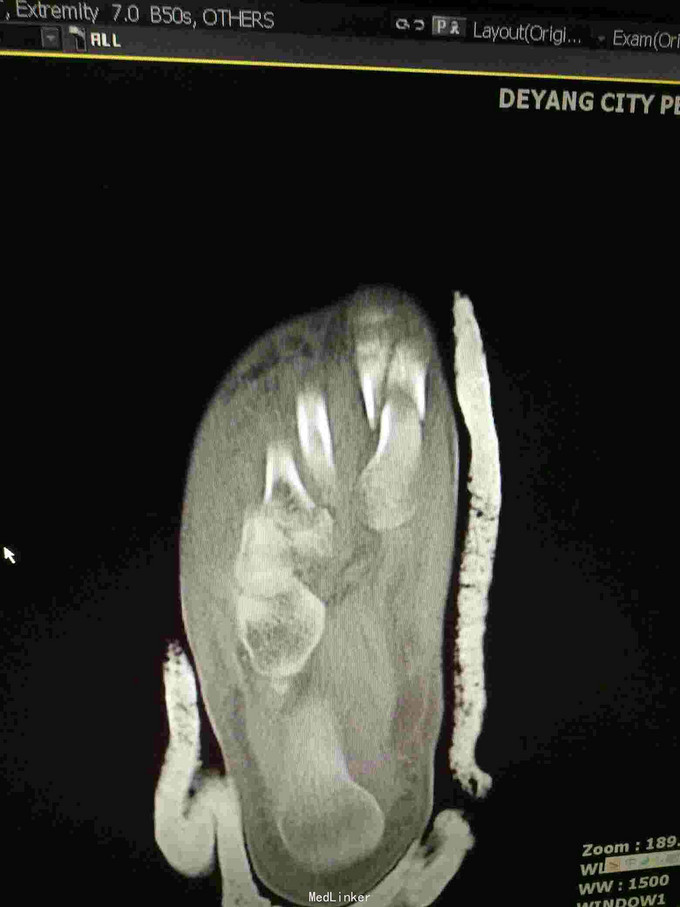

主诉:重物砸伤致右足疼痛伴活动受限2小时; 病史:患者不慎被重物砸伤右足,即感疼痛,活动受限,不能行走,不办皮肤破溃及活动性出血。

查体:右足畸形肿胀,足背少许擦挫伤,无开放性伤口,明显压痛,右足远远端感觉及血运可。 x片:右足第1、2跖骨基底部骨折,第3跖骨基底部可疑骨折; ct:右足第1~4跖骨骨折。

诊断:右足第1、2跖骨粉碎性骨折;右足lisfrance损伤; 治疗:石膏固定,消肿止痛,行右足跖骨骨折切开复位内固定,第1跖骨钢钉及克氏针固定,第2跖骨钢板固定。